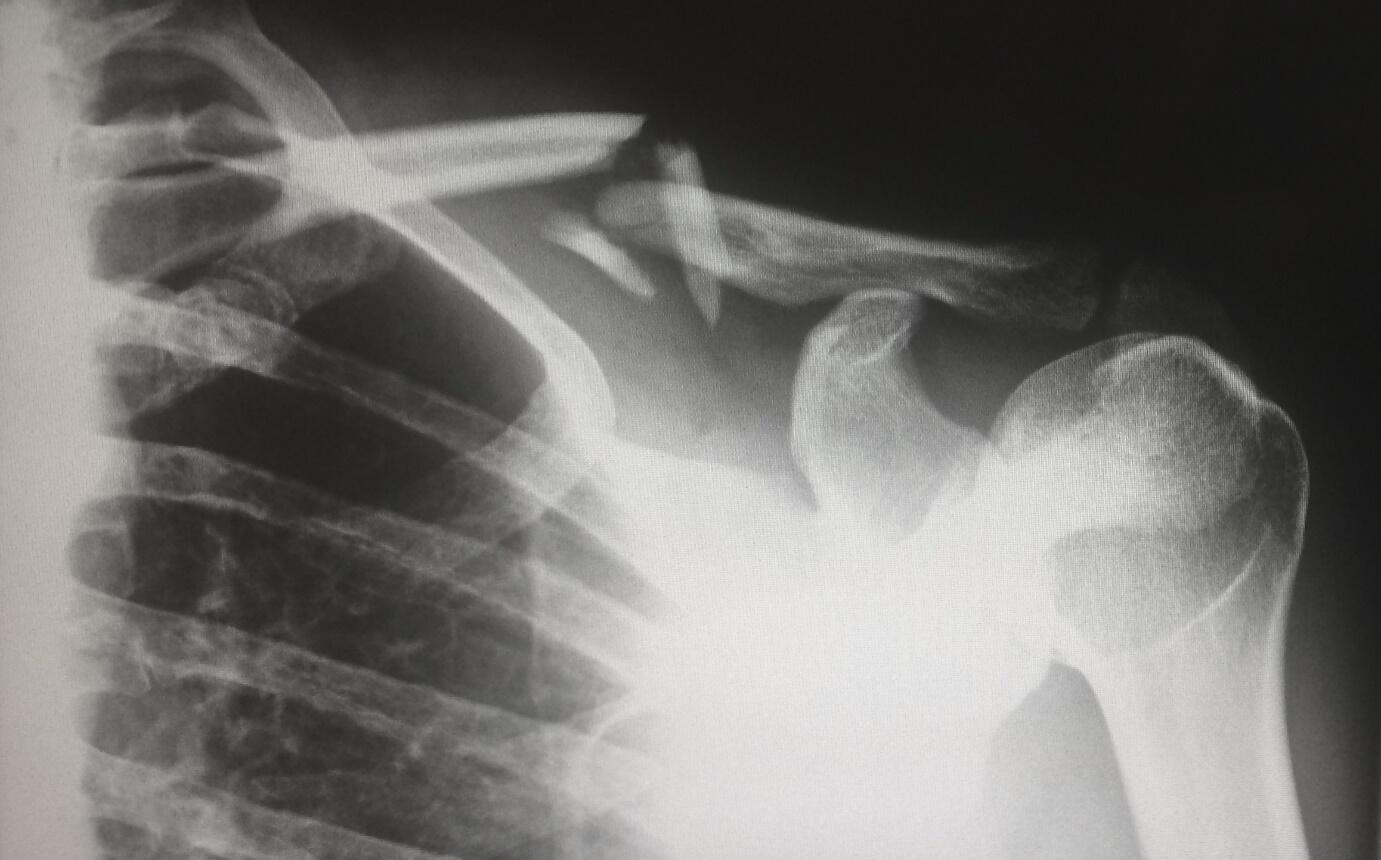

Personal injury cases often involve complex medical issues. It is crucial to acquire a working knowledge of medical terminology, common injuries, and their long-term effects.

Collaborating with medical professionals and attending seminars or workshops can deepen your understanding of medical aspects, enabling you to advocate for your client’s rights effectively.